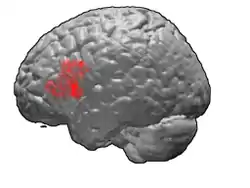

Frontal view.

Lateral view.

Lateral surface of left cerebral hemisphere, viewed from the side. (shown in orange).